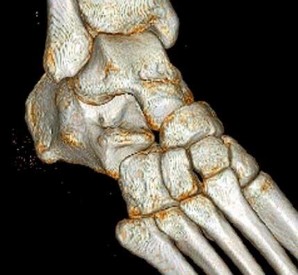

QUESTION 7

Figures 7a through 7h

1

Normal foot

2

Calcaneonavicular (CN) coalition

3

Talocalcaneal (TC) middle facet coalition

4

TC posterior facet coalition

Figure 7a shows a mild flatfoot with lateral peritalar subluxation of the navicular. Figure 7b does not show an open MF and has a questionable C sign. Figure 7c shows that the opening between the calcaneus and the navicular appears normal without distortion. Figures 7d, 7e, 7g, and 7h show a lateral sloping distorted middle facet consistent with a middle facet coalition, and Figure 7f shows a normal posterior facet.